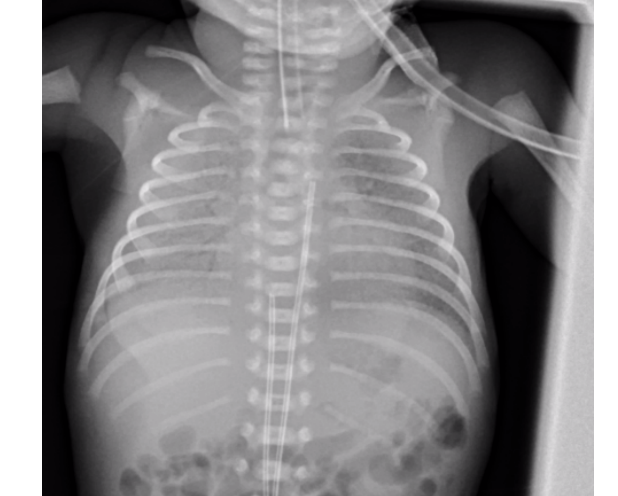

aappearance of HMD in chest x-ray

ground glass